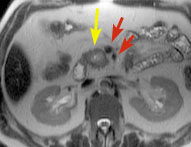

Sub-second transverse T2-weighted image shows the mass (yellow arrow), which does not involve the superior mesenteric artery and vein (red arrows).